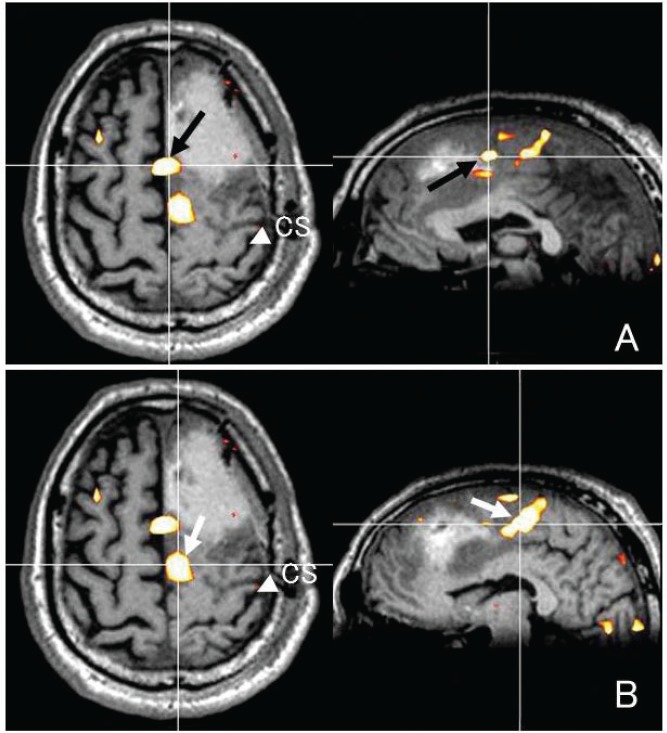

A 73-year-old man experienced a generalized seizure in January 2012. T1-weighted MRI depicted a low-intensity lesion with mild enhancement in the left superior and middle frontal lobes (Fig. 6A). T2-weighted MRI showed that the hyper-intense lesion partly involved the medial aspect of the superior frontal gyrus (Fig. 6B). LDT-SMA was adjacent to the lesion on fMRI analysis. We expected that total resection of the tumor may pose a risk of SMA injury. We, therefore, performed functional monitoring during awake craniotomy to minimize postoperative SMA syndrome.

Fig. 6.

A case with brain tumor in the left frontal lobe. A T1-weighted image with contrast medium reveals a small enhancement in the tumor center (A). A T2-weighted image demonstrating the hyperintense tumor mainly involved the superior frontal lobe, sparing the precentral gyrus (B). C and D were intraoperative neuronavigation images. White arrow and white arrowhead indicate the stimulation point of anterior (C) and posterior (D) part of the supplementary motor area activated during a lexical decision task, respectively.

LDT-SMA on fMRI was transferred to a neuronavigation system and fused with 3D T1-weighted MR images. ECS to the precentral and inferior frontal gyri with 7 mA of intensity evoked muscle cramps in the right hand and language-related symptoms such as speech arrest or paranomia, respectively. ECS to anterior part of LDT-SMA caused sudden speech arrest with no difficulties in verbal comprehension or movement of face, mouth, and tongue (Fig. 6C). ECS to posterior part of LDT-SMA with 7 mA of intensity evoked speech arrest and flaccid right hemiparesis of the upper and lower extremities (Fig. 6D). According to the SMA mapping, we determined resection borders. When the resection approached to anterior part of LDT-SMA on the neuronavigation, the patient was showing slow speech and mild dysarthria. Intraoperative frozen section diagnosis was low-grade glioma and our strategy was to make maximal resection of the lesion with no permanent neurological deficit. We confirmed that the planned resection was accomplished and finished the operation.

The patient temporarily suffered from motor aphasia with no hemiparesis for three postoperative days. Fusion images of preoperative fMRI and postoperative MRI demonstrated that the resection extended to the border of the anterior part of LDT-SMA (Fig. 7A–D).

Fig. 7.

Fusion of a preoperative functional magnetic resonance (fMR) image obtained while the subject was engaged in a lexical decision task (LDT) with a postoperative fMR image. These images reveal the relationship between the resection area or stimulating point and the anterior (A) or posterior (B) part of the supplementary motor area (SMA) activated during LDT (LDT-SMA). CS indicates the central sulcus.